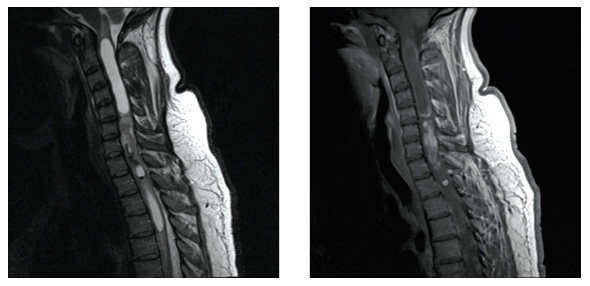

脊髓腫瘤,也稱椎管內(nèi)腫瘤(intraspinal tumors),是發(fā)生于脊髓本身及椎管內(nèi)與脊髓鄰近組織(脊神經(jīng)根、硬脊膜、脂肪組織、血管、先天性殘留組織等)的原發(fā)性腫瘤或轉(zhuǎn)移性腫瘤的總稱,通常也稱為脊髓腫瘤(spinal tumors)。

椎管內(nèi)腫瘤的發(fā)病率大約是顱內(nèi)腫瘤的1/10,發(fā)生于椎管的任何節(jié)段和病人的任何年齡段;除脊膜瘤外,男性發(fā)病率略高于女性。椎管內(nèi)腫瘤的組織學(xué)分類和分級(jí)與顱內(nèi)腫瘤一致,但良性腫瘤如神經(jīng)鞘瘤、脊膜瘤等發(fā)生率高,約占椎管內(nèi)腫瘤的3/4;同樣是膠質(zhì)瘤如髓內(nèi)室管膜瘤、星形細(xì)胞瘤級(jí)別比顱內(nèi)膠質(zhì)瘤低,預(yù)后較好。

1、髓內(nèi)腫瘤(Intramedullary Tumors)腫瘤起源于脊髓實(shí)質(zhì)部分(圖A),約占椎管內(nèi)腫瘤的5%-10%,其中膠質(zhì)瘤常見(jiàn),如室管膜瘤、星形細(xì)胞瘤,起次為血管母細(xì)胞瘤表皮樣囊腫、皮樣囊腫、畸胎瘤以及轉(zhuǎn)移瘤。

2、髓外硬脊膜內(nèi)腫瘤(Intradural Extramedullary Tumors)腫瘤位于脊髓外硬脊膜內(nèi)(圖B)。此類腫瘤較多,約占椎管內(nèi)腫瘤的65-70%,大多數(shù)為良性腫瘤,如神經(jīng)鞘瘤、脊膜瘤;少數(shù)為惡性腫瘤,如顱內(nèi)如室管膜瘤或髓母細(xì)胞瘤沿著蛛網(wǎng)膜下腔播散轉(zhuǎn)移。

3、硬脊膜外腫瘤(Extradural Tumors)腫瘤位于椎管內(nèi)硬脊膜外(圖C),約占椎管內(nèi)腫瘤的25%。大多數(shù)為惡性腫瘤,如轉(zhuǎn)移瘤、淋巴瘤和多發(fā)性骨髓瘤;少數(shù)為良性腫瘤如海綿狀血管瘤和肉芽腫。